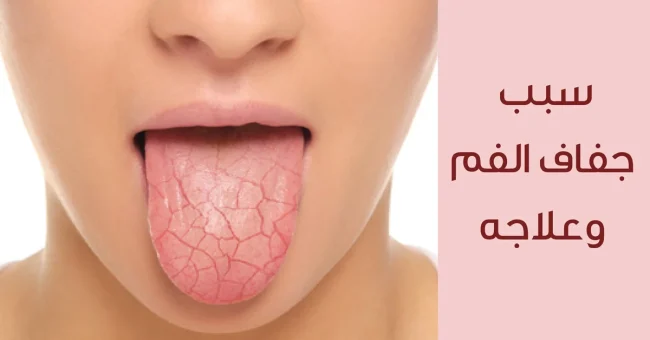

تعد صحة الفم و الأسنان جزءا لا يتجزأ من الصحة العامة للإنسان فهي تؤثر على مختلف جوانب الحياة اليومية بما في ذلك القدرة على التحدث تناول الطعام و صحة الجسد العامة و ايضا الثقة بالنفس. مع ذلك يواجه البعض مشكلات شائعة مثل عصب الأسنان المكشوف، و التي قد تسبب ألما بشكل كبير و تؤدي إلى…